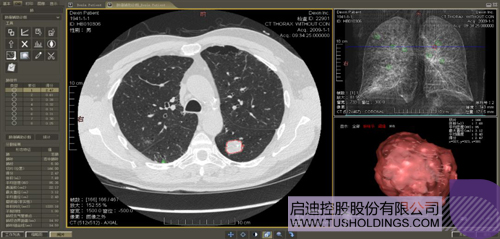

數(shù)字肺產(chǎn)品肺癌計(jì)算機(jī)輔助診斷

醫(yī)療影像智能分析是指運(yùn)用人工智能技術(shù)、計(jì)算機(jī)視覺技術(shù)以及計(jì)算幾何技術(shù)對(duì)醫(yī)療影像進(jìn)行自動(dòng)分析,幫助醫(yī)生定位病癥、分析、跟蹤病情,并通過量化數(shù)據(jù)輔助醫(yī)生做出診斷,目前其旗艦產(chǎn)品“數(shù)字肺”已經(jīng)覆蓋多種肺部疾病的早期檢測(cè)、診斷、跟蹤、術(shù)前規(guī)劃等完整的醫(yī)療流程。在臨床實(shí)踐中,超過80%的醫(yī)療數(shù)據(jù)來自醫(yī)療影像,這些影像數(shù)據(jù)通常需要專業(yè)醫(yī)生進(jìn)行解讀,工作的重復(fù)性高、效率偏低。如果能夠運(yùn)用智能影像分析技術(shù),同時(shí)結(jié)合臨床表現(xiàn)以及既往病例進(jìn)行全面分析,那么就可以大幅度提升影像診斷效率和準(zhǔn)確性,讓專業(yè)醫(yī)生的寶貴時(shí)間集中在復(fù)雜病情的診斷和治療等環(huán)節(jié)。

數(shù)字肺——肺結(jié)節(jié)手術(shù)規(guī)劃系統(tǒng)